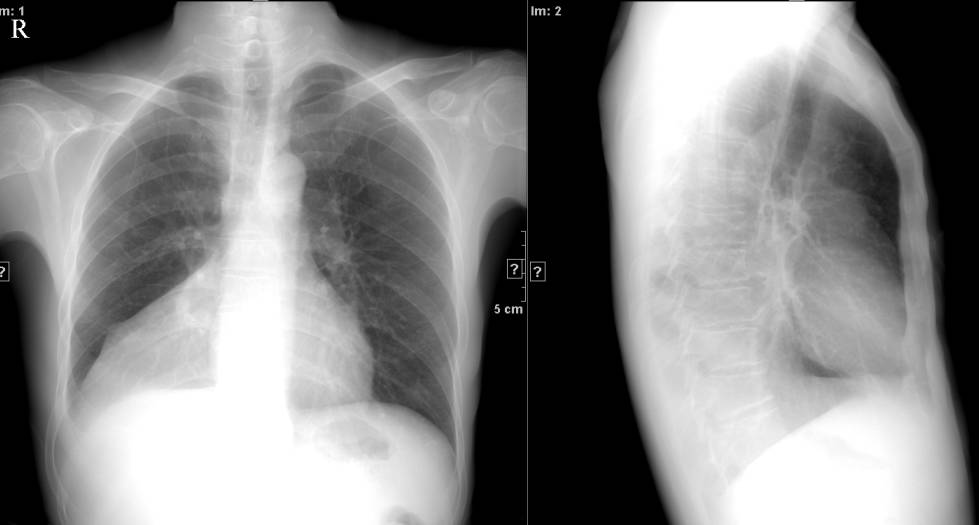

↓ 右肺中叶不张 ↓

↓ 右下内基底段肺不张 ↓